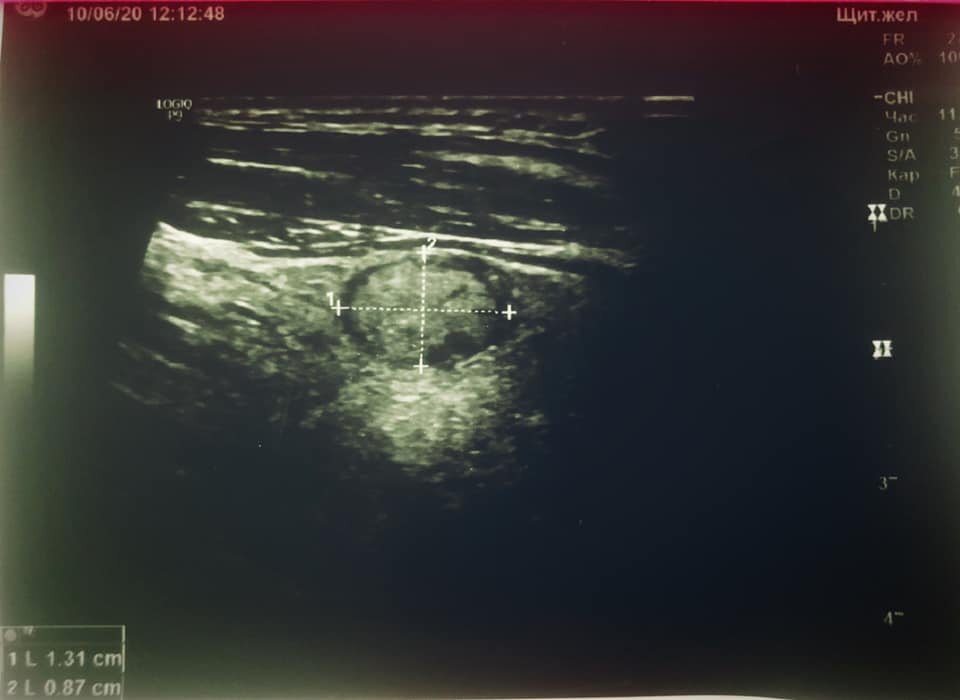

При ультразвуковом обследовании у пациента 56 лет обнаружен единичный узел щитовидной железы размером 13.1 х 8.7 х 15 мм. Вы видите этот овал, окруженный темным ободком? Это он и есть, наш узел. Чем больше в нем разноцветных включений, тем более он может нас настораживать. Если уж он есть, то пусть будет гомогенным (однородным), а всяческие неоднородности будят в нас ненужные подозрения и мысли. То, что он достиг размера более 1 сантиметра, заставляет нас сделать пункцию этого узла. И, хотя результаты пункции будут готовы через несколько дней, кое-какие первичные заключения сделать мы можем. А потом сравним. Смотрим на наружный контур черного ободка. Он ровный, без признаков "кляксовидности" и смазанности. Это хорошо. По его внутреннему контуру - единичные мелкие ярко-белые включения: это микрокальцинаты, говорящие о "старости" узла. Ему несколько лет. Наличие таких же мелких точек по центру узла, в его "серой" части, а также мелких овальных черных вкраплений на 4 - 5 часах услов

Смотрим на наружный контур черного ободка. Он ровный, без признаков "кляксовидности" и смазанности. Это хорошо. По его внутреннему контуру - единичные мелкие ярко-белые включения: это микрокальцинаты, говорящие о "старости" узла. Ему несколько лет. Наличие таких же мелких точек по центру узла, в его "серой" части, а также мелких овальных черных вкраплений на 4 - 5 часах условного циферблата (представьте узел в виде часов со стрелками и ориентируйтесь на часовые зарубки) - говорит о внутренних процессах, произошедших в этом узле за все время его существования: это микрокальцинаты и мелкие кисточки (зоны кистозной трансформации).

А еще в хороших аппаратах УЗИ есть функция исследования сосудов, и при включении сосудистого режима я обнаружила, что узел имеет как периферическую сосудистую подпитку, так и собственный кровоток. Здесь тоже есть некоторые тонкости: степень и глубина распространения сосудов (не глубже 1/3 толщины узла), максимальная скорость кровотока - 11 см/с и ИР 0.60 - индекс резистивности - говорят о доброкачественной природе узла.